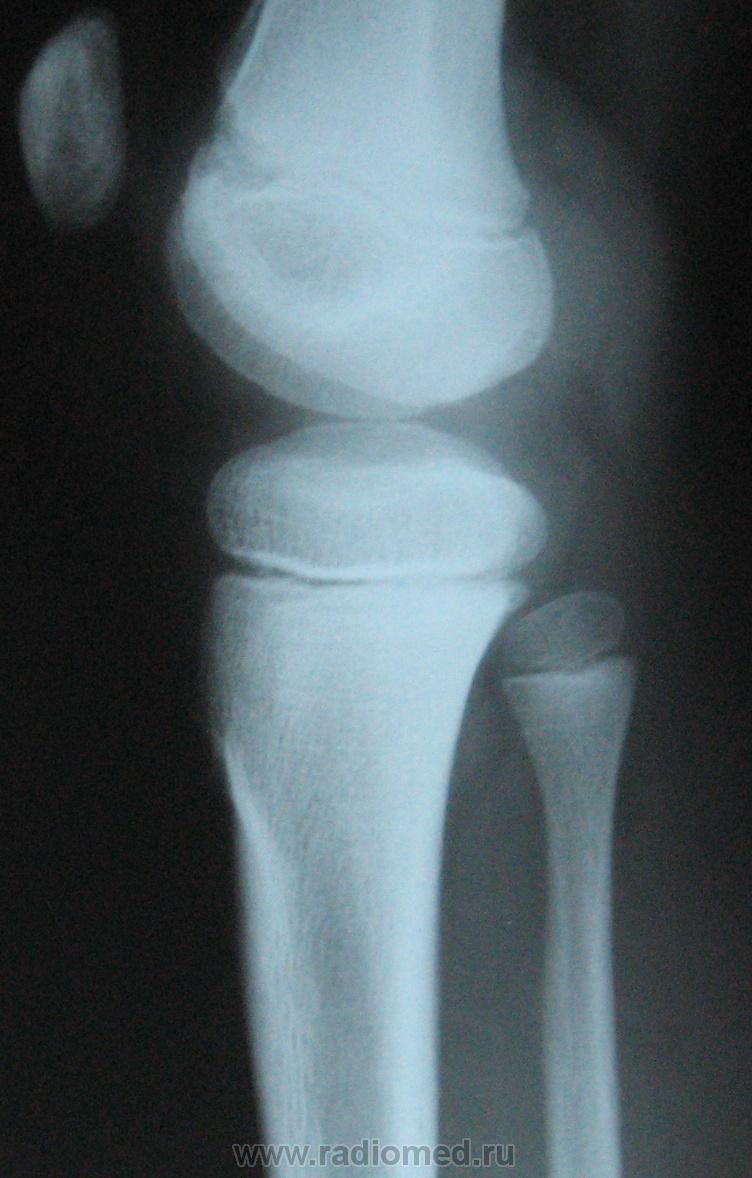

Мальчик 10 лет. Травма 1 год назал ( сомнительная).  4 мес. назад обнаружили плотное образование в обл. бугристости бб. кости. За это время увеличелось на 13. При пальпации очень плотное, без болезненное, не подвижное. Ваше мнение? Нужна ли активная хирургическая тактика?

С учётом клиники, можно предположить, что речь идёт болезни Осгуд-Шляттера, хотя привычной картины для этой болезни не видно на снимке. А, что за метод представлен на 3 слева снимке?

Я однажды наблюдала рост костно-хрящевого экзостоза из бугристости большеберцовой кости. Возможно, здесь тоже самое.

А что за участок разрежения в метафизе бедра?

Согласен с коллегой. Весьма "интересный" участок в области дистального метафиза бедренной кости.

Если на на снимке не визуализируется,  но при этом образование как вы пишите плотное и имеет место быть атрофии кортикала от давления, можно предположить о хондроме.

А ведь "тенюху" то видно она на широком основании,  ещё возможно хрящевой экзостоз.

Возможно, на структурном снимке и будет видна тень. Хорошо видна нечеткость контура кортикального слоя по переднему контуру б/берцовой кости в области проксимального метафиза.

Полность с Вами согласен. Но на мой взгляд необходимо также произвести качественные рентгенограммы и данного сустава в стандартных проекциях, а возможно и в косых проекциях. Возможно целесообразна и прицельная рентгенография с центрацией на "болевую точку" или на точку пальпируемого "что-то".

А мне что-то не кажется это нормальным вариантом ростковой зоны, и надколенник здесь как бы отодвинут от бедра (в прямой проекции его вовсе не видно). А что думают об этом наши любимые детские рентгенологи?

А ведь Петрович ПРАВ! Надколенник смещен кпереди и весьма неравномерно - верхние отделы надколенника смещены кпереди больше, по сравнению с нижними. По всей видимости, что-то "невидимое" отодвигает надколенник кпереди. А что у нас "невидимое" - может "бяка", состоящая из хрящевой ткани?

Мне кажется, с надколенником все нормально, на счет ростковой зоны....не знаю, сомнительно. Я бы рекомендовала снять вторую ногу, и потом уже думать.

Я возьму на себя ответственность произвести качественные снимки в стандартных проекциях, а возможно и в нестандартных. Автор случая, фактически не представил рентгенограммы в прямой проекции. Имеем только боковую и её-же фрагмент с увеличением.

Не совсем понял.... Так мы сможем увидеть рентгенограмму контрлатерального сустава? Ещё хотелось бы увидеть прямую проекцию целиком. И, наконец, предел желаний, боковая проекция этого сустава, сделанная для мягких тканей: выдержку экспозиции надо уменьшить в 3-4 раза.